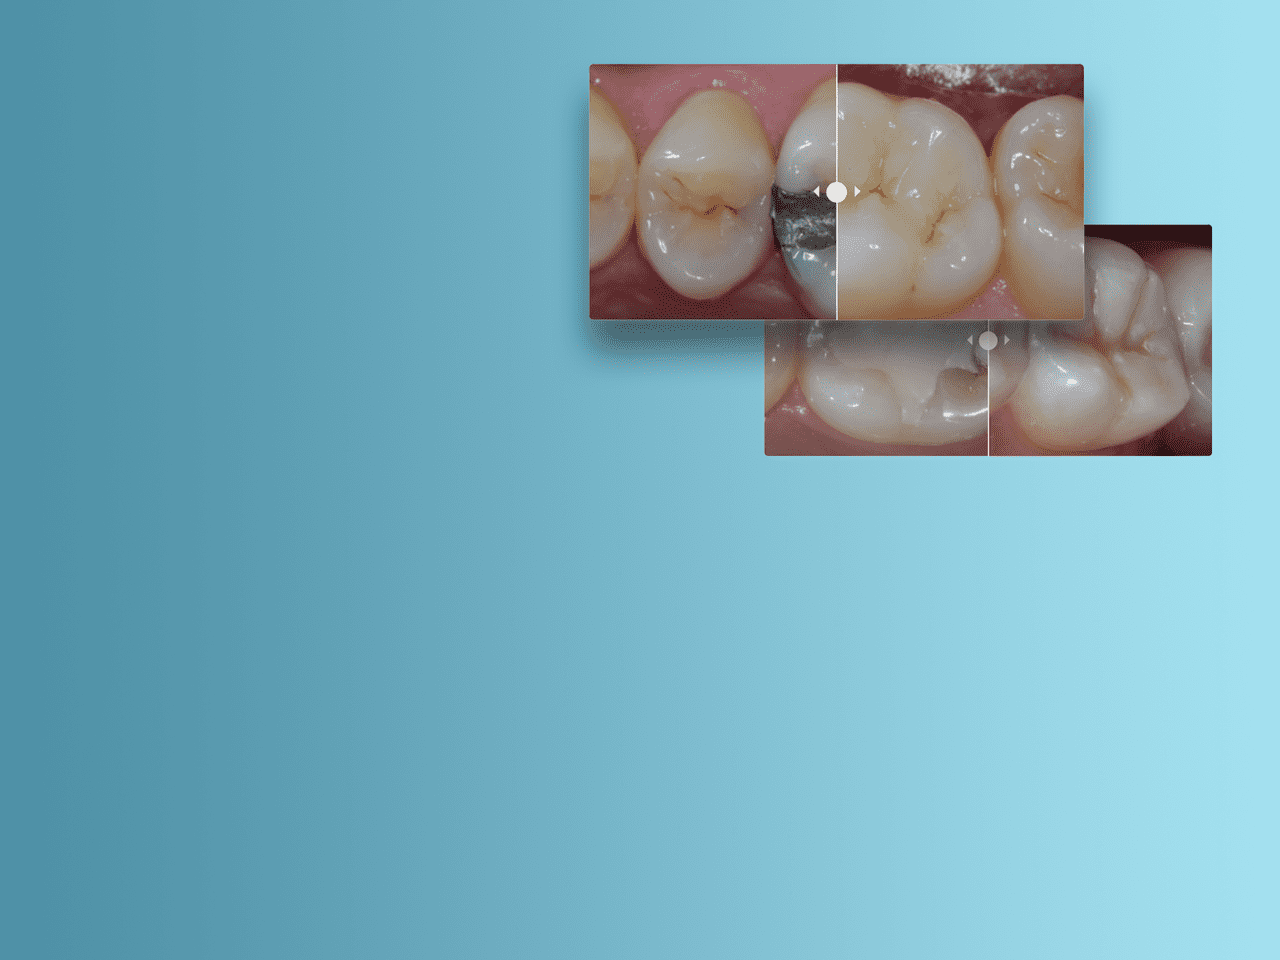

Bild:

Vorher: Posteriore Restauration mit A2-Farbton des Spectra ST Restaurationskomposits (Quelle: Dr. A. Ferrando)

Nachher: Amalgam-Ersatz mit fortschrittlicher Schichttechnik unter Verwendung von A2 und Bleach White-Farbton des Spectra ST Restaurationskomposits